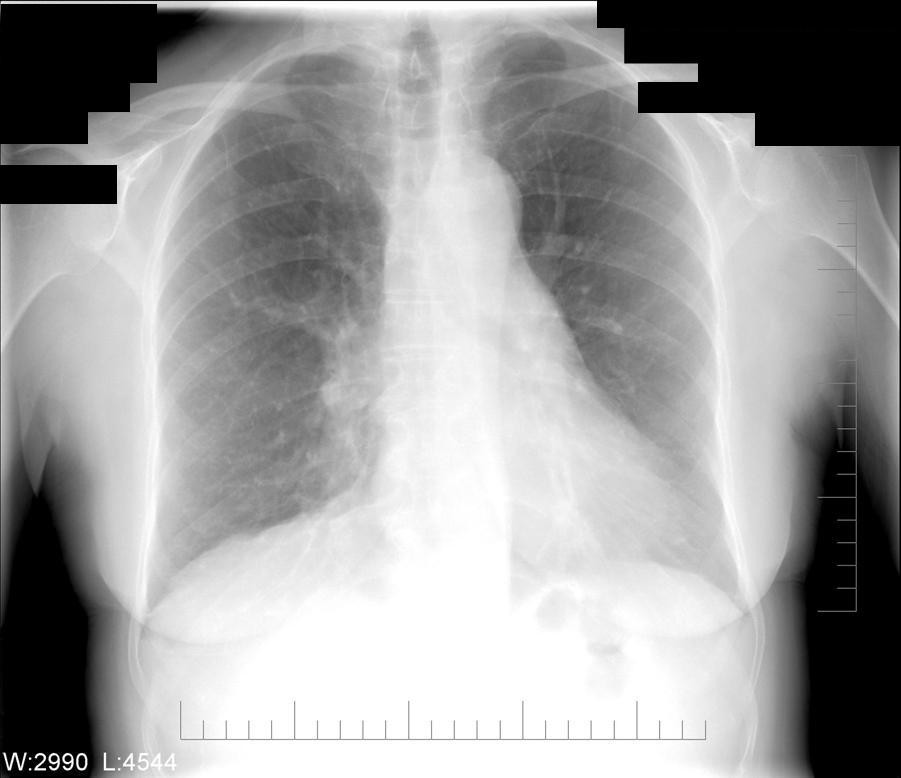

Reading The Chest XRay (Chest Radiography) Identifying A Normal Chest Smoke Inhalation Radiographs smoke inhalation injury is a complex multifaceted lung and systemic disease process, which until recently, has. inhalation injury is a broad term that includes pulmonary exposure to a wide range of chemicals in various forms including smoke, gases,. The index of suspicion for smoke inhalation injury is. our findings indicate that the standard chest radiograph is an. Smoke Inhalation Radiographs.

The serial chest radiographs of the patient Download Scientific Diagram Smoke Inhalation Radiographs smoke inhalation is diagnosed in patients that have a history of exposure to smoke and fire events. inhalation injury is a broad term that includes pulmonary exposure to a wide range of chemicals in various forms including smoke, gases,. smoke inhalation injury is a complex multifaceted lung and systemic disease process, which until recently, has. our. Smoke Inhalation Radiographs.